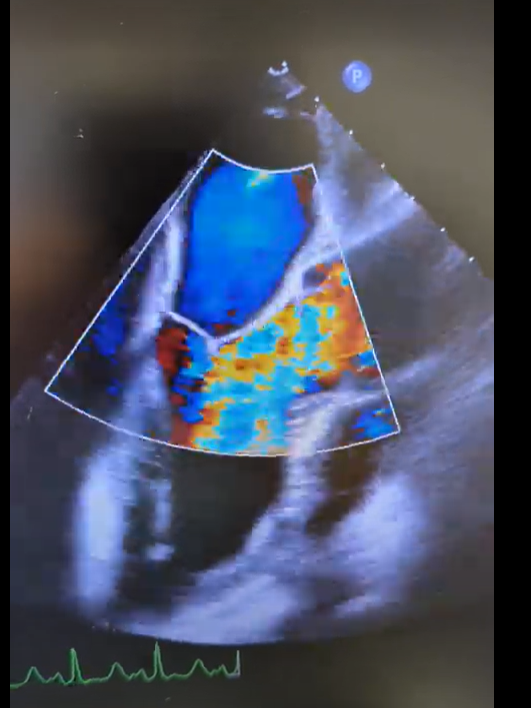

Pretty much spot on. The gifs didn't capture the way I would've liked (they're kinda choppy), but if you squint real hard you'll notice in the 4ch color shot that there is a central jet and a highly, eccentric anteriorly directed jet. There ended up being a cleft plus myxomatous degeneration leading to both Carpentier type I and II mechanisms.